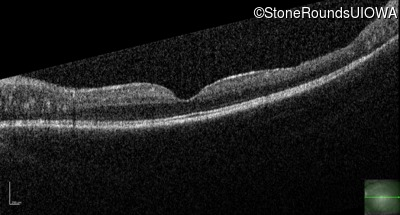

Optical Coherence Tomography - Right - 20/50

Exemplar / OCT Stack